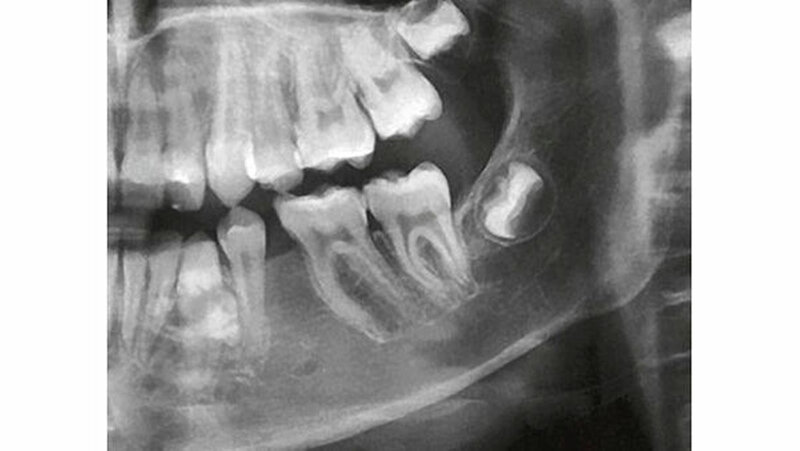

Ein 16-jähriger Patient wurde von seinem Zahnarzt aufgrund einer langsam aber stetig größer werdenden knöchernen Vorwölbung am Alveolarfortsatz regio 32-34 lingual zur diagnostischen Abklärung und entsprechenden Therapie an die Klinik für Mund-, Kiefer-, Gesichtschirurgie und Oralchirurgie des Luzerner Kantonsspitals in Luzern überwiesen. Anamnestisch war der Patient gesund, subjektiv hatte er keine Beschwerden. Eine kieferorthopädische Behandlung war ein Jahr zuvor abgeschlossen worden, wobei bei der radiologischen Routinekontrolle zufällig eine radioopake Veränderung im Bereich der Wurzeln der Zähne 33 und 34 imponierte.

Der extraorale Befund zeigte eine normale Sensibilität der Unterlippe. Intraoral am Alveolarfortsatz des linken Unterkiefers regio 32-34 lingual konnte eine circa 2×2,5 cm große, schmerzreie knöcherne Vorwölbung palpiert werden (Abbildung 1). Die Zähne 31-36 reagierten normal auf den Test mit CO2-Schnee.